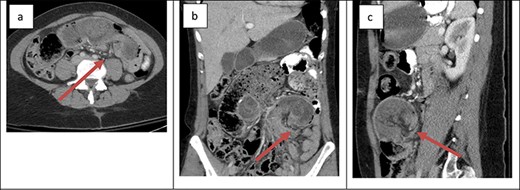

The second patient was a 41-year-old female with a history of open Roux-en-Y gastric bypass ~20 years prior and abdominoplasty with bilateral breast augmentation. Her only medication was Contrave to treat weight regain after bariatric surgery. She was 400 lbs at the time of her surgery and 185 lbs at time of presentation. The patient presented with an 8-h history of severe abdominal pain. The patient also reported two episodes of vomiting and two bowel movements prior to presentation. Her vitals were within the normal limits and laboratory work was unremarkable. Physical examination revealed a soft abdomen with a palpable mass at the site of tenderness in the left lower quadrant. Cross-sectional imaging revealed retrograde intussusception at the jejunojejunal anastomosis (Fig. 2); the cross-sectional imaging was also suggestive of hepatic vein thrombosis that was ruled out with a hepatic duplex ultrasound. The patient was taken emergently to the operating room for laparoscopic lysis of adhesions and reduction of intussusception. The involved small bowel measured ~30 cm in length and appeared grossly viable so no formal resection or revision was performed at the time of operation. The patient’s post-operative course was uncomplicated. She was started on clear liquids on POD#1 and discharged home on POD#2. The patient reported that she was symptom free at her 1-week post-operative office appointment.

Cross-sectional imaging of displaying bowel and mesentery (arrow) intussuscepting into the JJ anastomosis on (a) transverse view, (b) coronal view and (c) sagittal view.

The presentation of intussusception is widely variable depending on the severity of the disease process. Common presentations include abdominal pain, nausea and vomiting, new palpable abdominal mass, lower GI bleeding and signs of sepsis. Intussusception can be diagnosed through various imaging modalities such as cross-sectional imaging, plain radiographs, small bowel series and ultrasonography. Cross-sectional imaging is believed to be not only highly sensitive but also reliable [3]. On cross-sectional imaging, intussusception appears as a complex soft tissue mass representing bowel telescoped onto itself often with an eccentric area of hypoattenuation within the mass representing the intussuscepted mesenteric fat [5]. The pathognomonic appearance is appreciated in Figs 1 and 2. Furthermore, the wall of the internalized loop of bowel can be observed within the dilated bowel when imaging is enhanced with intravenous contrast. Prompt diagnosis and surgical intervention are paramount in management of intussusception.